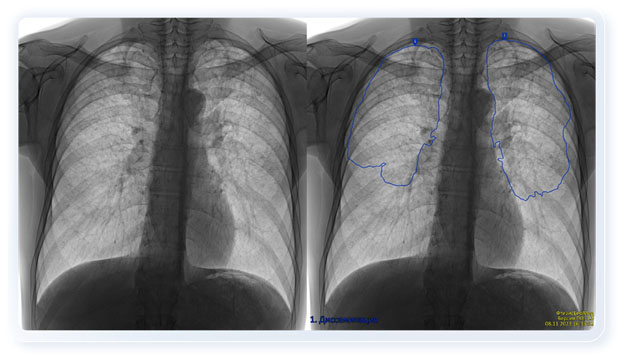

Dịch vụ FthizisBioMed cung cấp khả năng chẩn đoán tự động các bệnh lý của cơ quan lồng ngực như: lao, ung thư, bệnh tim mạch, COVID-19 và các bệnh khác với độ chính xác rất cao. Thời gian phân tích một ảnh chụp X-quang hoặc phim chụp huỳnh quang của dịch vụ FthizisBioMed là 0,8 giây.

Dịch vụ có thể được sử dụng dưới hình thức điện toán đám mây. Điều này có nghĩa là bất kỳ bác sĩ X-quang nào tại bệnh viện ở Việt Nam đều có thể, từ thiết bị X-quang của mình, gửi hình ảnh chụp qua internet lên nền tảng đám mây và trong vòng 15–20 giây sẽ nhận được các khuyến nghị chẩn đoán từ dịch vụ FthizisBioMed cho bệnh nhân của mình.